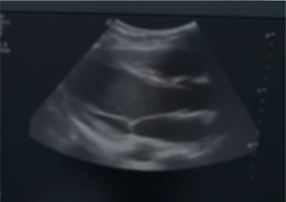

3D 입체 초음파로

피부, 피하지방층, 근육, 신경 등

연부 조직의 위치와 두께를

정밀하게 측정